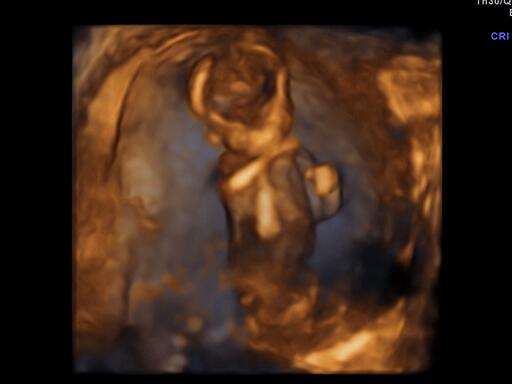

@nijka jeeej. to je 3D?

@figurka1985 hej hej chvilu sme vcera pozerali aj takto 😉

@figurka1985 zial nevideli lebo to naše bábo bolo príliš akčné a ani pofotit sa nedalo a ze niektoré zábery boli fakt krásne. Mali sme to v ramci screeningu za 30eur a teta dr.nam tie fotky nejaké dala aj na USB plus jednu 3D taký trošku vacsi rozmer ako klasika nam aj vytlačila. 😉